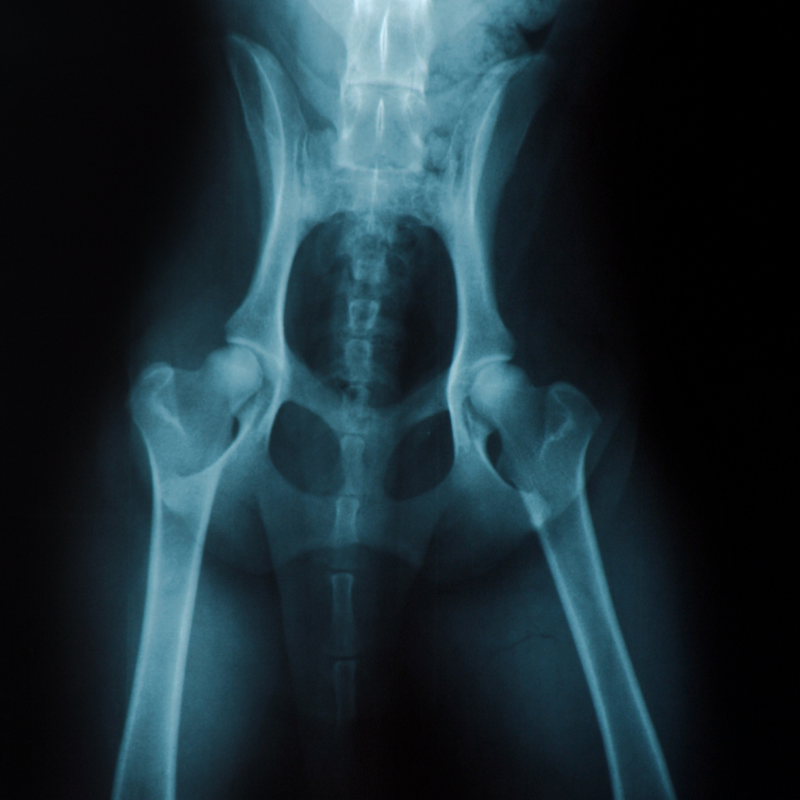

Arthrose ist eine schmerzhafte Erkrankung der Gelenke, die bei Hunden häufig vorkommt. Es gibt verschiedene Ursachen, die dazu führen können, dass Hunde an Arthrose erkranken.

Arthrose äußert sich durch Gelenkschmerzen, die ein Hund durch Hinken, Steifheit und Lahmheit zeigen kann.

Ein weiteres Symptom ist eine eingeschränkte Beweglichkeit des Gelenks sowie Schmerzen bei Berührung oder Druck auf das Gelenk.